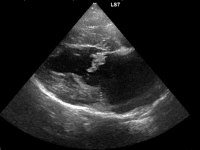

肺水腫